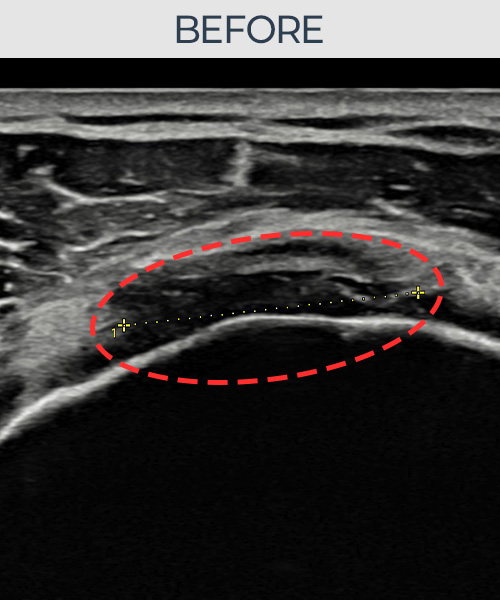

최ㅇㅇ님 · 우측 극상근건 점액낭면측 부분파열

우측 어깨 통증이 수개월간 지속되어 내원하셨습니다. 초음파 검사에서 점액낭면측 극상근건 부분파열이 확인되었으며, 어깨인대 축소봉합술 후 힘줄 두께가 회복되고 에코 연속성이 정상화되었습니다.